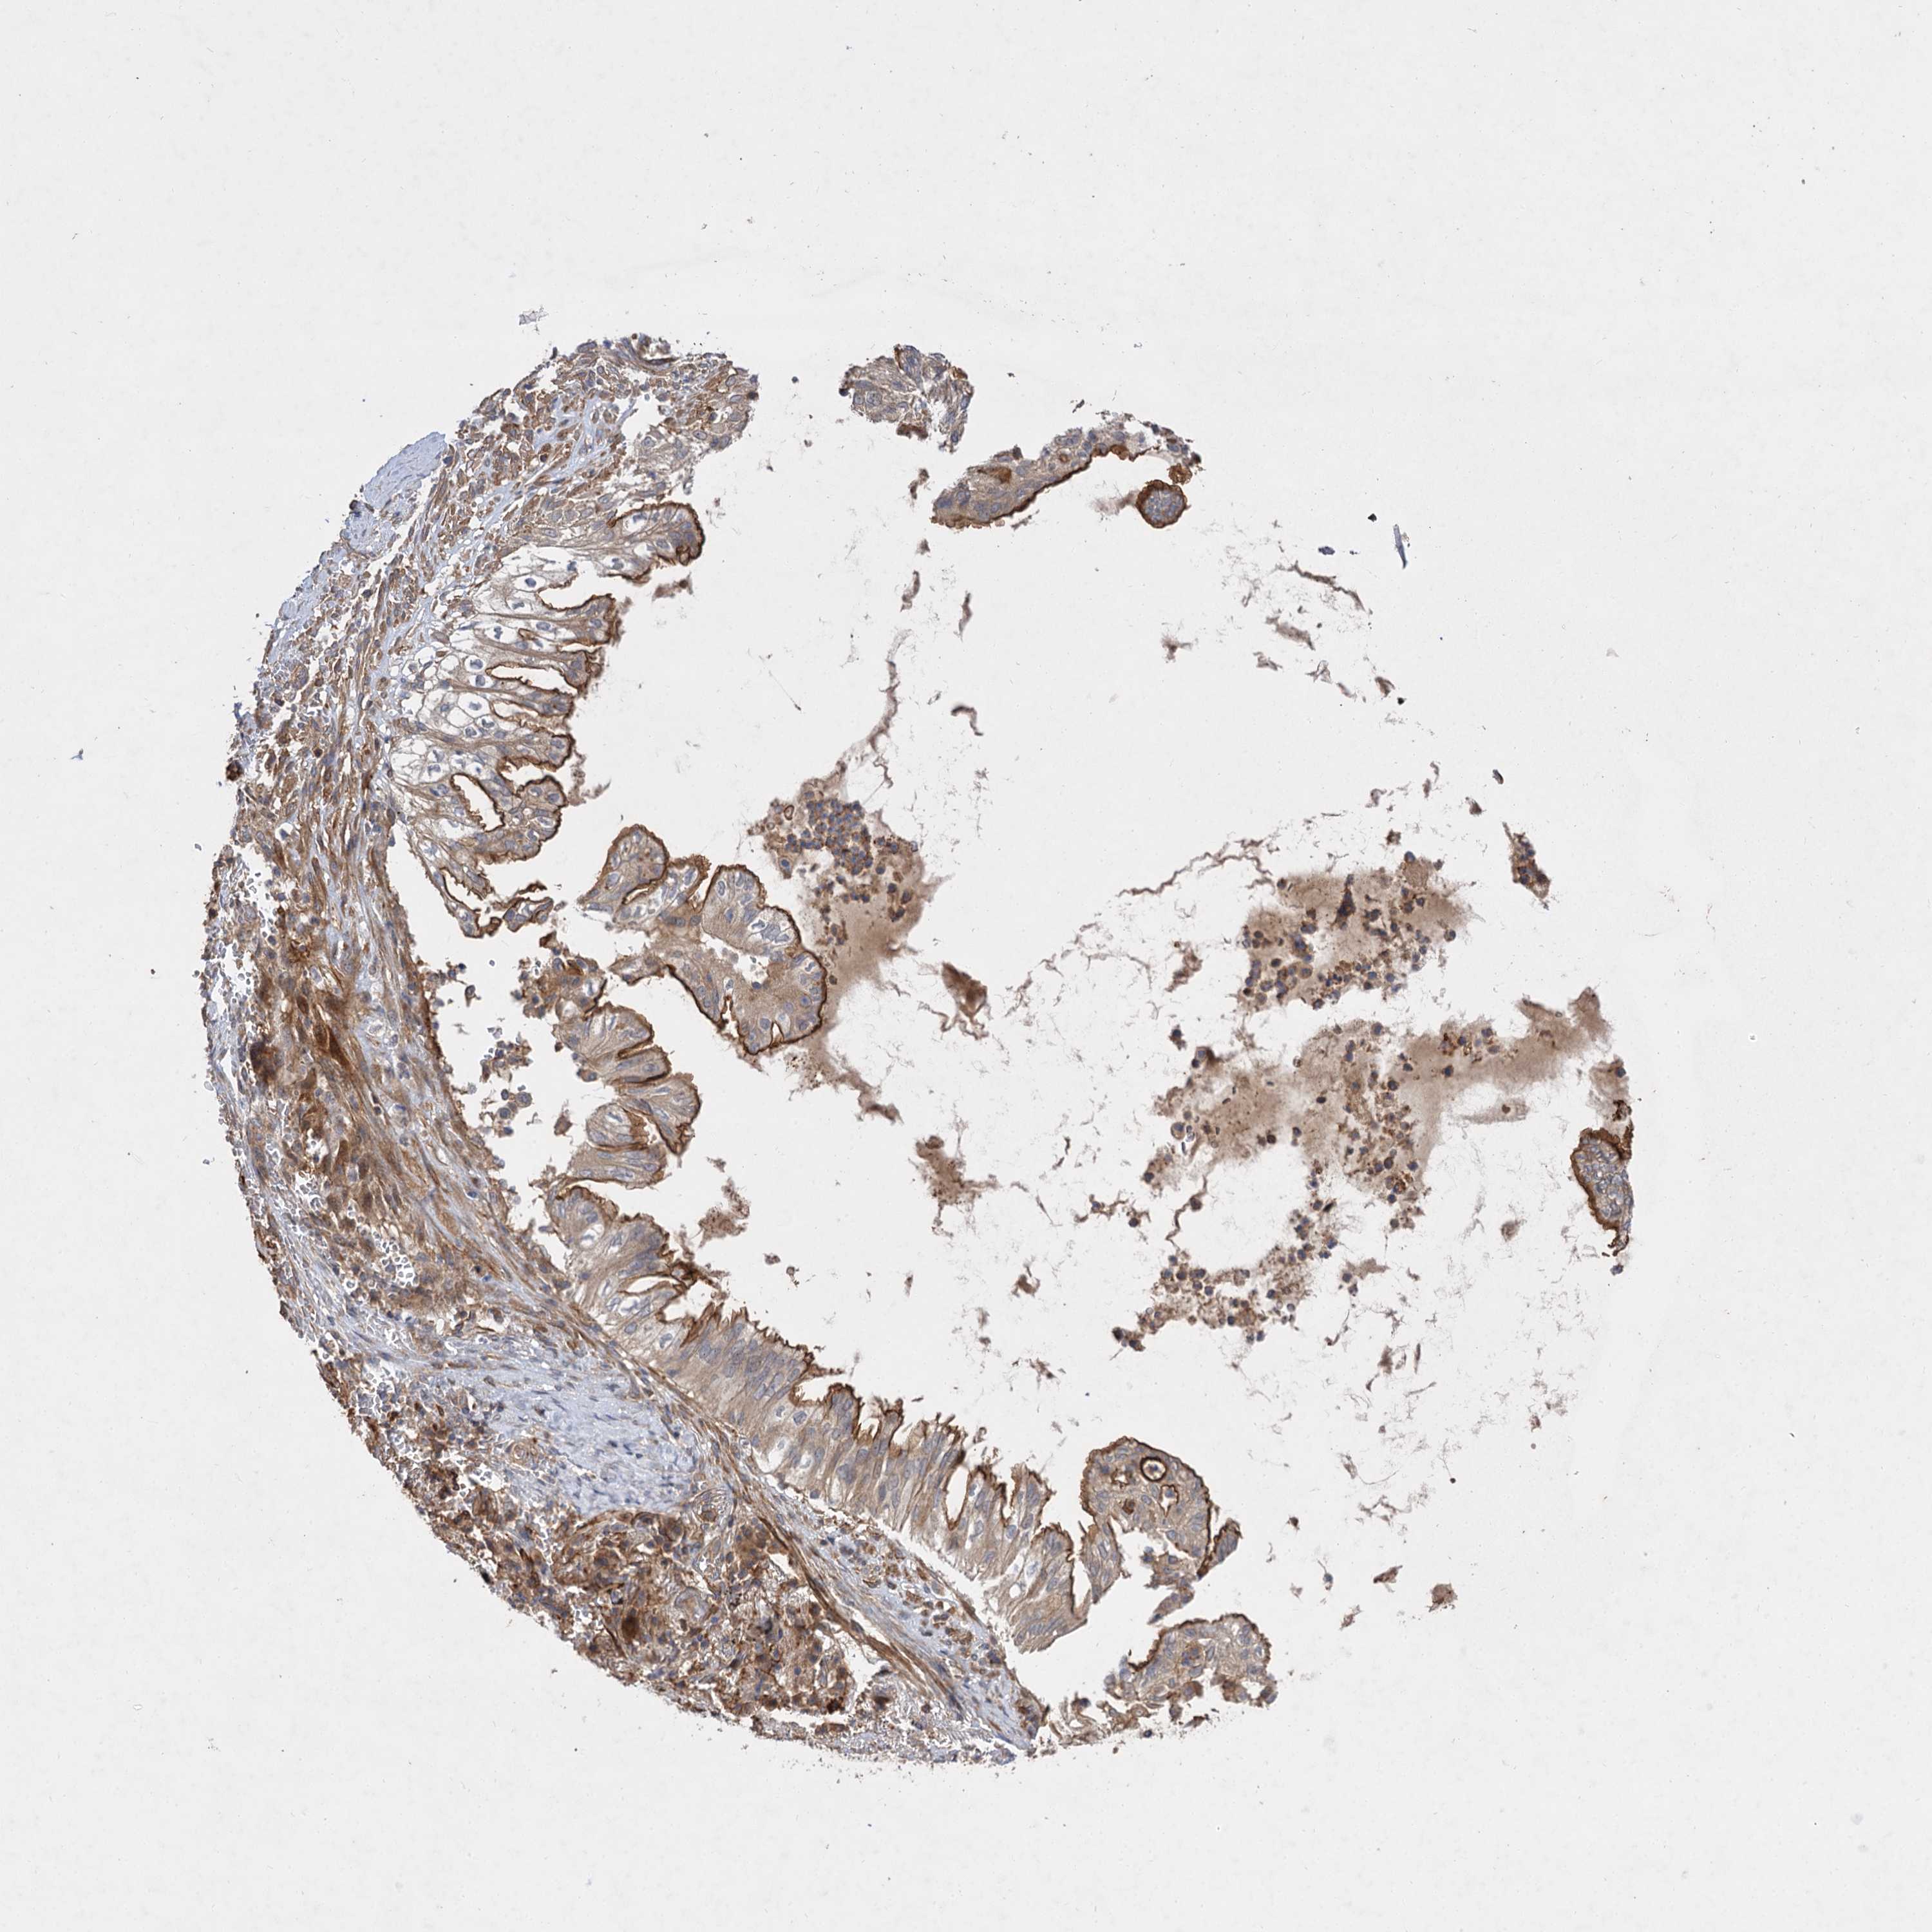

TCGA-34-2608-01A 84 years, male, white, stage:Stage IB, dead, 1000 days 6.0

TCGA-98-A53C-01A 77 years, female, white, stage:Stage IA, alive, 822 days 6.0

TCGA-77-8139-01A 72 years, male, stage:Stage IIB, alive, 3166 days 6.0

TCGA-94-A5I4-01A 61 years, male, white, stage:Stage IIA, alive, 491 days 5.9

TCGA-77-8156-01A 60 years, male, stage:Stage IB, alive, 1106 days 5.9